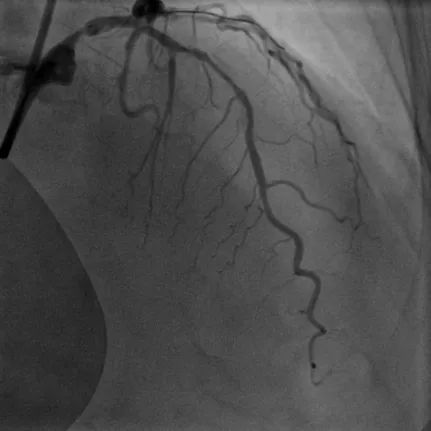

病例3

LM-LAD钙化病变:患者73岁女性,主因胸痛2小时入院,既往高血压病史,诊断不稳定型心绞痛。该患者1周前因心绞痛入院,CAG显示RCA95%狭窄伴血栓,于RCA植入一枚支架。患者左主干严重钙化病变狭窄80%,合并LAD弥漫钙化最重处狭窄90%,精准充分预处理格为重要,姚朱华主任团队综合评估患者病情后决定择期IVUS指导下行Shockwave冲击波球囊治疗。IVUS检查显示LM-LAD弥漫性钙化,最重处360°环形钙化,应用3.5*12mm Shockwave冲击波球囊顺利到达病变处,自LAD中段至LM末端连续释放脉冲,在左主干处释放4个周期(40个脉冲),成功于LM-LAD植入3枚支架,术后IVUS评估达到理想的支架膨胀及贴壁效果。

术前冠脉造影